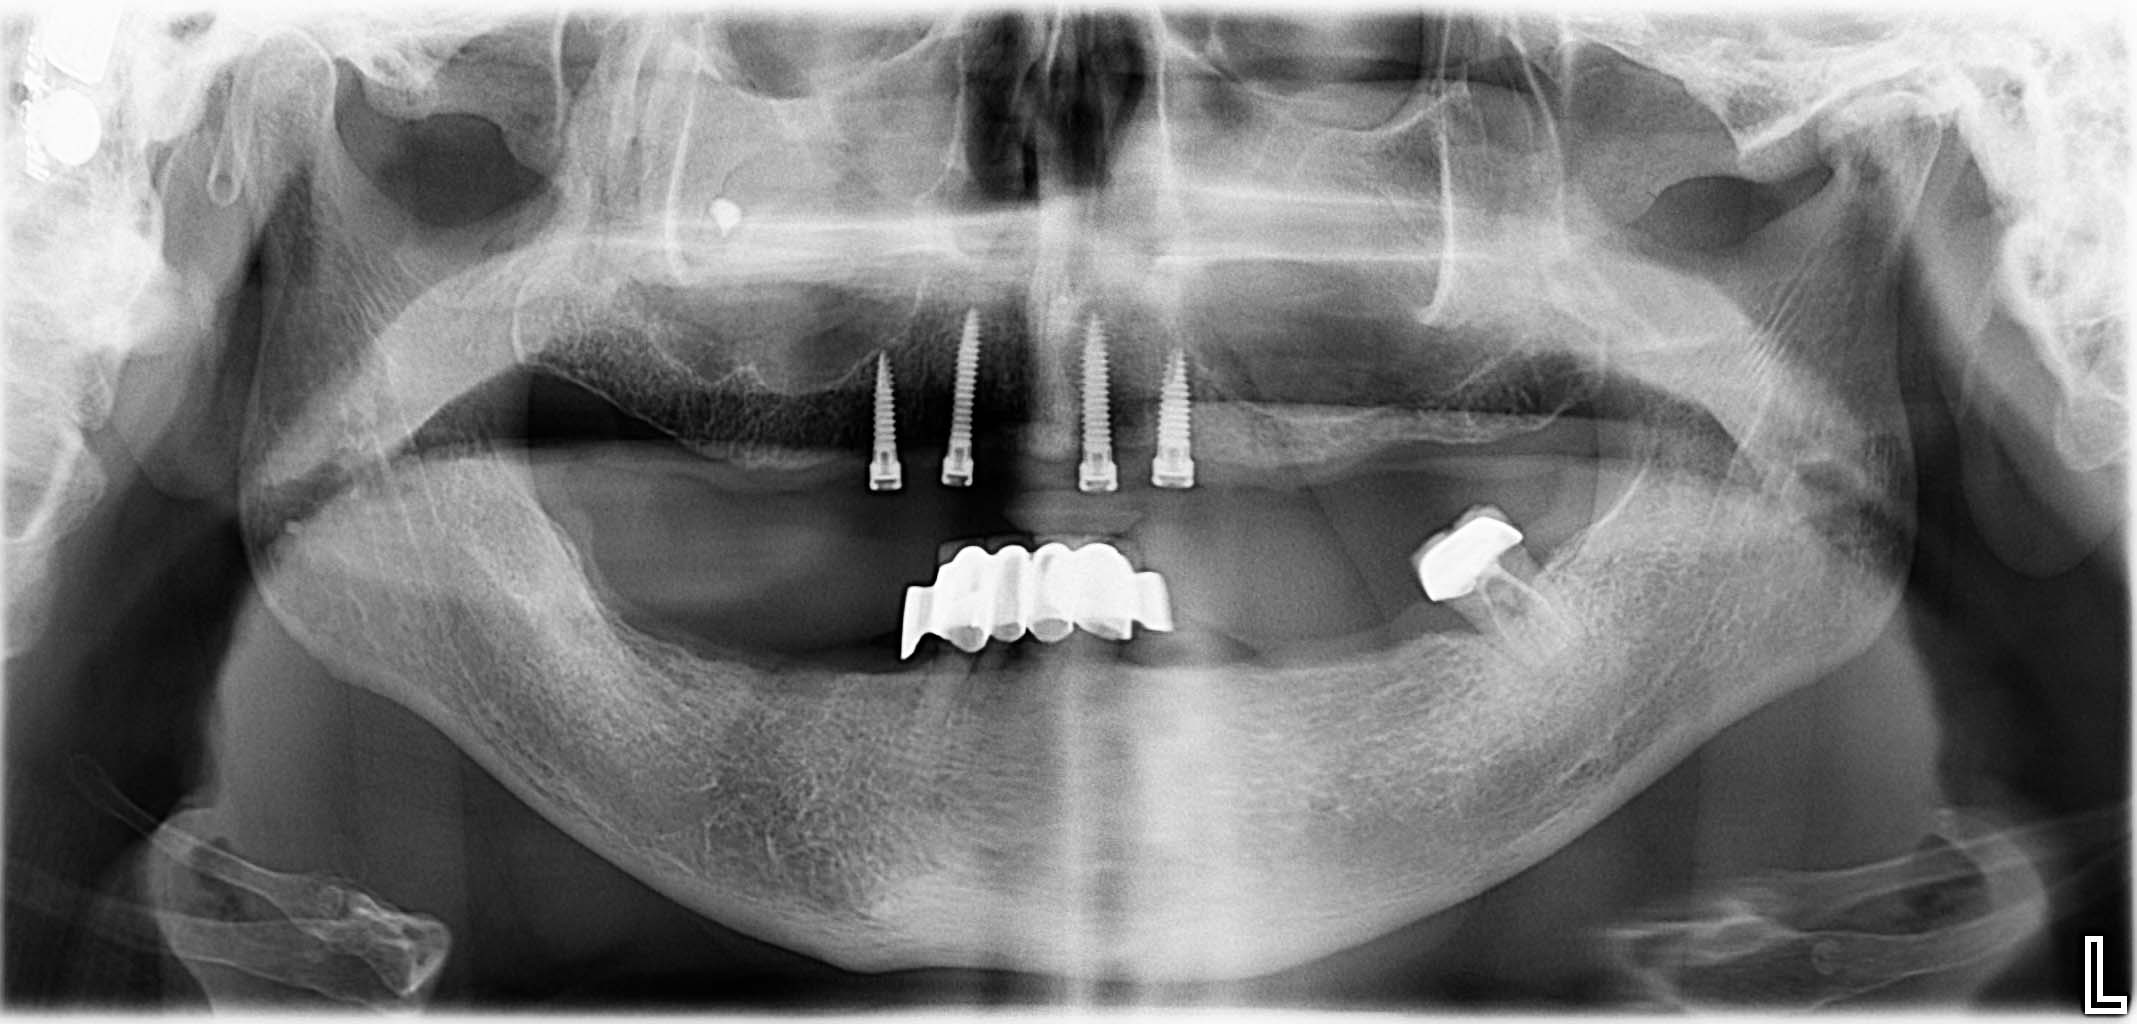

Erfolgreich implantierte Patientenfälle (klinische Fotos)